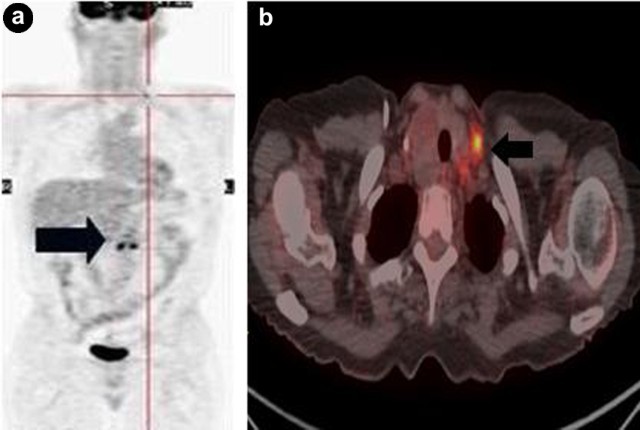

Pancreatic cancer uses TNM system, which stands for tumor (T), nodal involvement (N), and metastases (M), for staging. Stage I disease is confined to the pancreas. Stage II is extended outside the pancreas. Stage III is involved with lymph nodes. Stage IV is characterized by distant metastases. PET is more accurate than CT for M staging because it allows better detection of distant metastasis (Figure 1) and provides greater ability of differentiating benign from malignant behavior of equivocal lesions on CT. Approximately 1/3 of small metastases (<1 cm) in the liver and peritoneum were missed by CT and MRI. A meta-analysis showed that PET/CT had the highest pooled sensitivity (91%) in detecting peritoneal metastases when compared to CT and MRI [2]. PET/CT has an accuracy of 91% for primary pancreatic lesions, 85% for loco-regional staging, and 92% for restaging of pancreatic cancer [3]. PET/CT changes care management of patients (36-41% of cases) by providing a more accurate staging of pancreatic cancer [1].

|

Figure 1. a. Coronal PET maximum intensity projection image detects a distant left supraclavicular nodal metastasis (crosshair) of pancreatic cancer (arrow). b. Fused axial PET/CT image shows the corresponding left supraclavicular node (arrow). PET/CT provides an accurate M staging that is not obtainable with other conventional cross-sectional imaging modalities. |